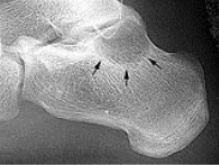

What do the arrows show? | Stress fracture |